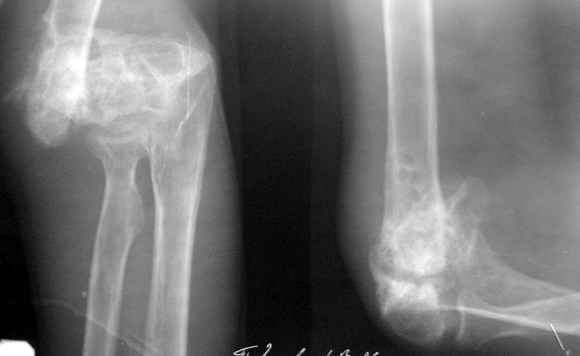

Obviously there is no elbow joint...the options are few: (from the worst to the "best"...if any)

1. Arthrodesis - last choice if at all

2. If no pain leave it as it is

3. Total elbow replacement (semi constrained - as no ligaments to stabilize the joint) - Coonrad-Morrey, Discovery - Biomet - considering his age there is limited indication for that procedure.

4. There is limited experience with total elbow allograft replacement with some rate of successes on one hand and high rate of complications on the

other hand. I personally would try this option as it is a reversible procedure and one could in a case of failure to replace it with prosthesis